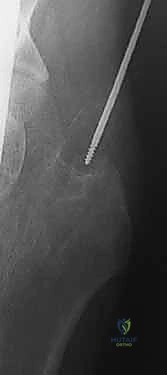

كسر عنق الفخذ: العلاج الحديث بالمسامير المجوفة عبر الجلد مع الأستاذ الدكتور محمد هطيف في صنعاء

كسر عنق الفخذ هو إصابة خطيرة تتطلب تدخلاً جراحيًا دقيقًا. يعتمد العلاج الفعال على التثبيت بالمسامير المجوفة عبر الجلد، وهي تقنية حديثة تضمن استعادة استقرار المفصل وتعزيز الشفاء. يقدم الأستاذ الدكتور محمد هطيف في صنعاء خبرة رائدة في هذا المجال لتحقيق أفضل النتائج للمرضى.

الخلاصة الطبية السريعة: يُعد كسر عنق الفخذ (Femoral Neck Fracture) من الإصابات العظمية المعقدة والخطيرة التي تتطلب تدخلاً جراحيًا دقيقًا وسريعًا لتجنب المضاعفات الوخيمة مثل النخر اللاوعائي لرأس الفخذ. يعتمد العلاج الفعال والحديث على التثبيت الجراحي باستخدام "المسامير المجوفة عبر الجلد" (Percutaneous Cannulated Screws)، وهي تقنية جراحية طفيفة التوغل تضمن استعادة استقرار المفصل، تقليل تلف الأنسجة، وتعزيز الشفاء السريع. يقدم الأستاذ الدكتور محمد هطيف، استشاري جراحة العظام والمفاصل في صنعاء وأستاذ جراحة العظام بجامعة صنعاء، خبرة رائدة تمتد لأكثر من 20 عامًا في هذا المجال، مستخدمًا أحدث التقنيات الجراحية الدقيقة لتحقيق أفضل النتائج الحركية والوظيفية للمرضى.

التثبيت بالمسامير المجوفة عبر الجلد (Percutaneous Cannulated Screws): ثورة في جراحة العظام

تُعد تقنية التثبيت باستخدام المسامير المجوفة (Cannulated Screws) المعيار الذهبي لعلاج كسور عنق الفخذ غير المزاحة (Garden I & II) لدى جميع الأعمار، والكسور المزاحة التي يمكن ردها بنجاح لدى الشباب والبالغين.

هي مسامير طبية متطورة مصنوعة من التيتانيوم (Titanium) أو الفولاذ المقاوم للصدأ (Stainless Steel). السمة المميزة لها هي وجود "تجويف" أو نفق يمتد عبر مركز المسمار بالكامل. هذا التصميم العبقري يسمح للجراح بإدخال سلك توجيهي رفيع (Guide Wire) أولاً في العظم لتحديد المسار الدقيق، ثم يتم تمرير المسمار المجوف فوق هذا السلك لينزلق مباشرة إلى المكان المحدد بدقة مليمترية.

لماذا نستخدم 3 مسامير؟ (هندسة المثلث المقلوب)

يعتمد الأستاذ الدكتور محمد هطيف على مبادئ الميكانيكا الحيوية (Biomechanics) في التثبيت. يتم عادةً إدخال ثلاثة مسامير متوازية في عنق الفخذ. لا يتم وضعها بشكل عشوائي، بل تُرتب في شكل مثلث مقلوب (Inverted Triangle):

1. المسمار السفلي (Inferior Screw): يُوضع أولاً ليكون الدعامة الأساسية التي تستند على الكورتيكس السفلي الصلب لعنق الفخذ (Calcar)، وهو يتحمل أكبر قدر من وزن الجسم.

2. المسمار الأمامي العلوي (Antero-superior Screw).

3. المسمار الخلفي العلوي (Postero-superior Screw).

هذا التوزيع الثلاثي يوفر ثباتًا دورانيًا (Rotational Stability) ممتازًا ويمنع رأس الفخذ من الانزلاق أو الدوران حول محوره، كما يسمح بانضغاط الكسر (Compression) على طول خط الكسر، مما يحفز الخلايا العظمية على الالتئام السريع.

مميزات التثبيت عبر الجلد (Percutaneous Technique)

- تدخل جراحي طفيف (Minimally Invasive): لا يتم عمل شق جراحي كبير لفتح العضلات والأنسجة، بل يتم إدخال المسامير عبر شقوق جلدية صغيرة جدًا (حوالي 1-2 سم لكل مسمار).

- الحفاظ على التروية الدموية: عدم فتح محفظة المفصل يقلل من خطر الإضرار بالأوعية الدموية المتبقية التي تغذي رأس الفخذ.

- ألم أقل بكثير: نظرًا لعدم قطع العضلات الكبيرة، يكون الألم بعد العملية في حده الأدنى.

- شفاء أسرع: خروج أسرع من المستشفى وتأهيل حركي مبكر.